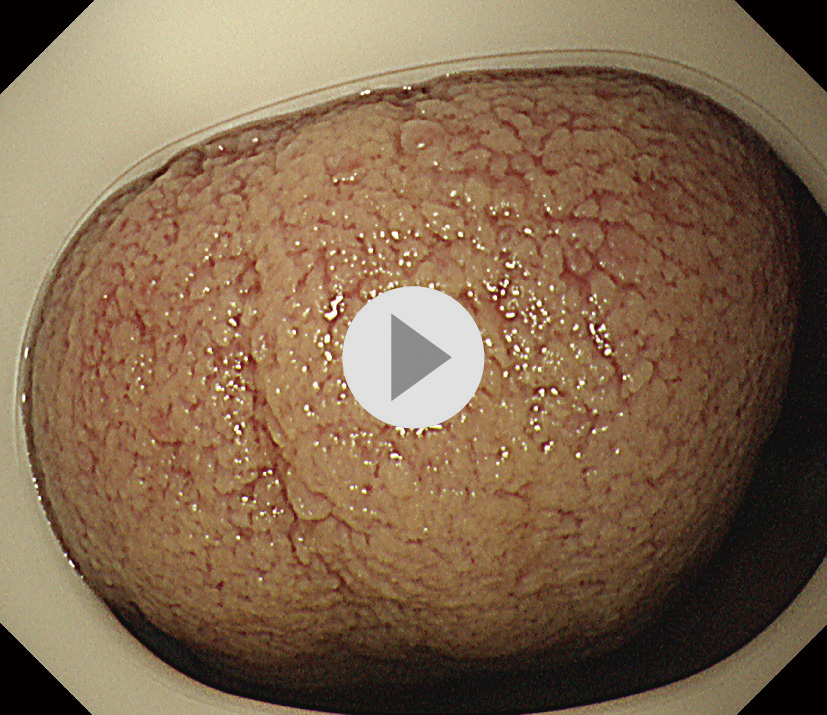

内視鏡画像:ⓔ動画11-1-5 (144枚の静止画を連続再生)

内視鏡検査所見・診断:report (図2) 参照

検査時間:12分

撮影枚数:144枚

生検結果:Group 1 fundic gland polyp